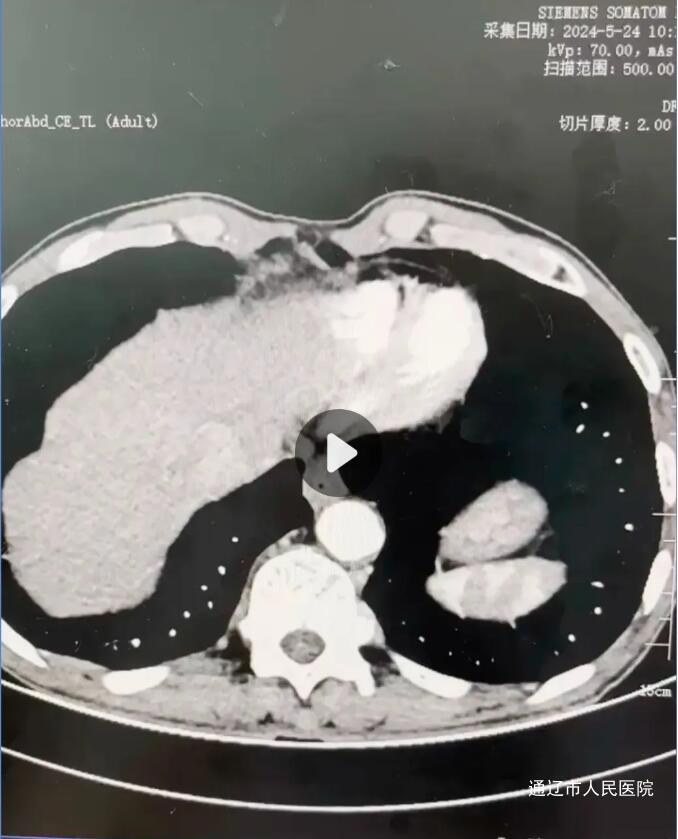

术前CT

腹部增强CT